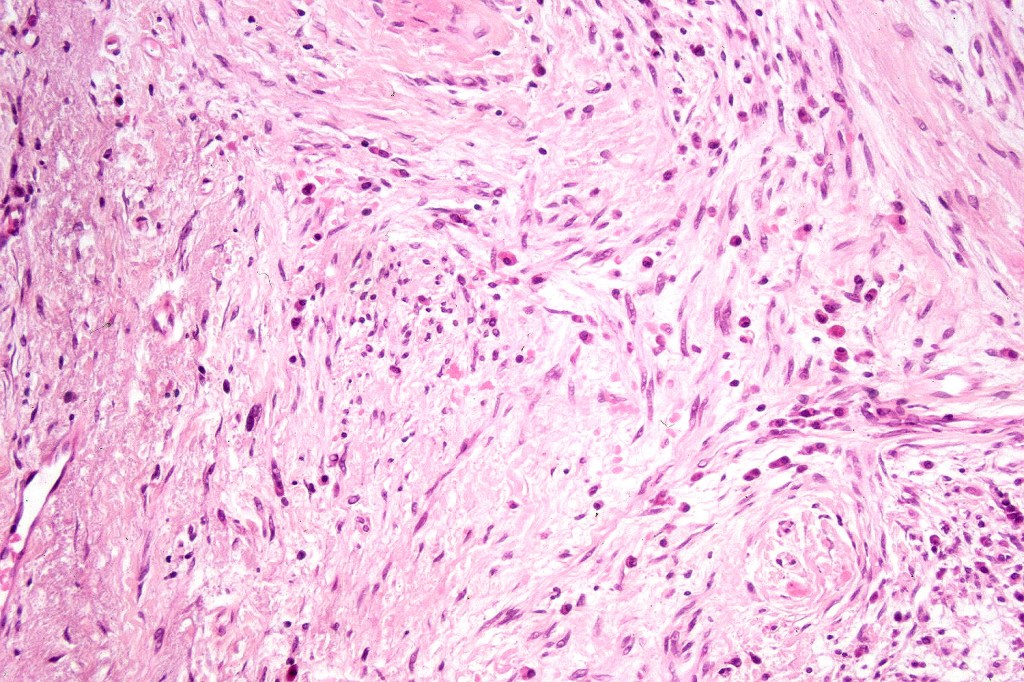

Histological features

•Paucicellular spindle cell infiltrate with “myxoid” fine to a dense collagenous stroma

•Hyperchromatic nuclei

•Variable pleomorphism

•Neurotropism

•Neural transformation